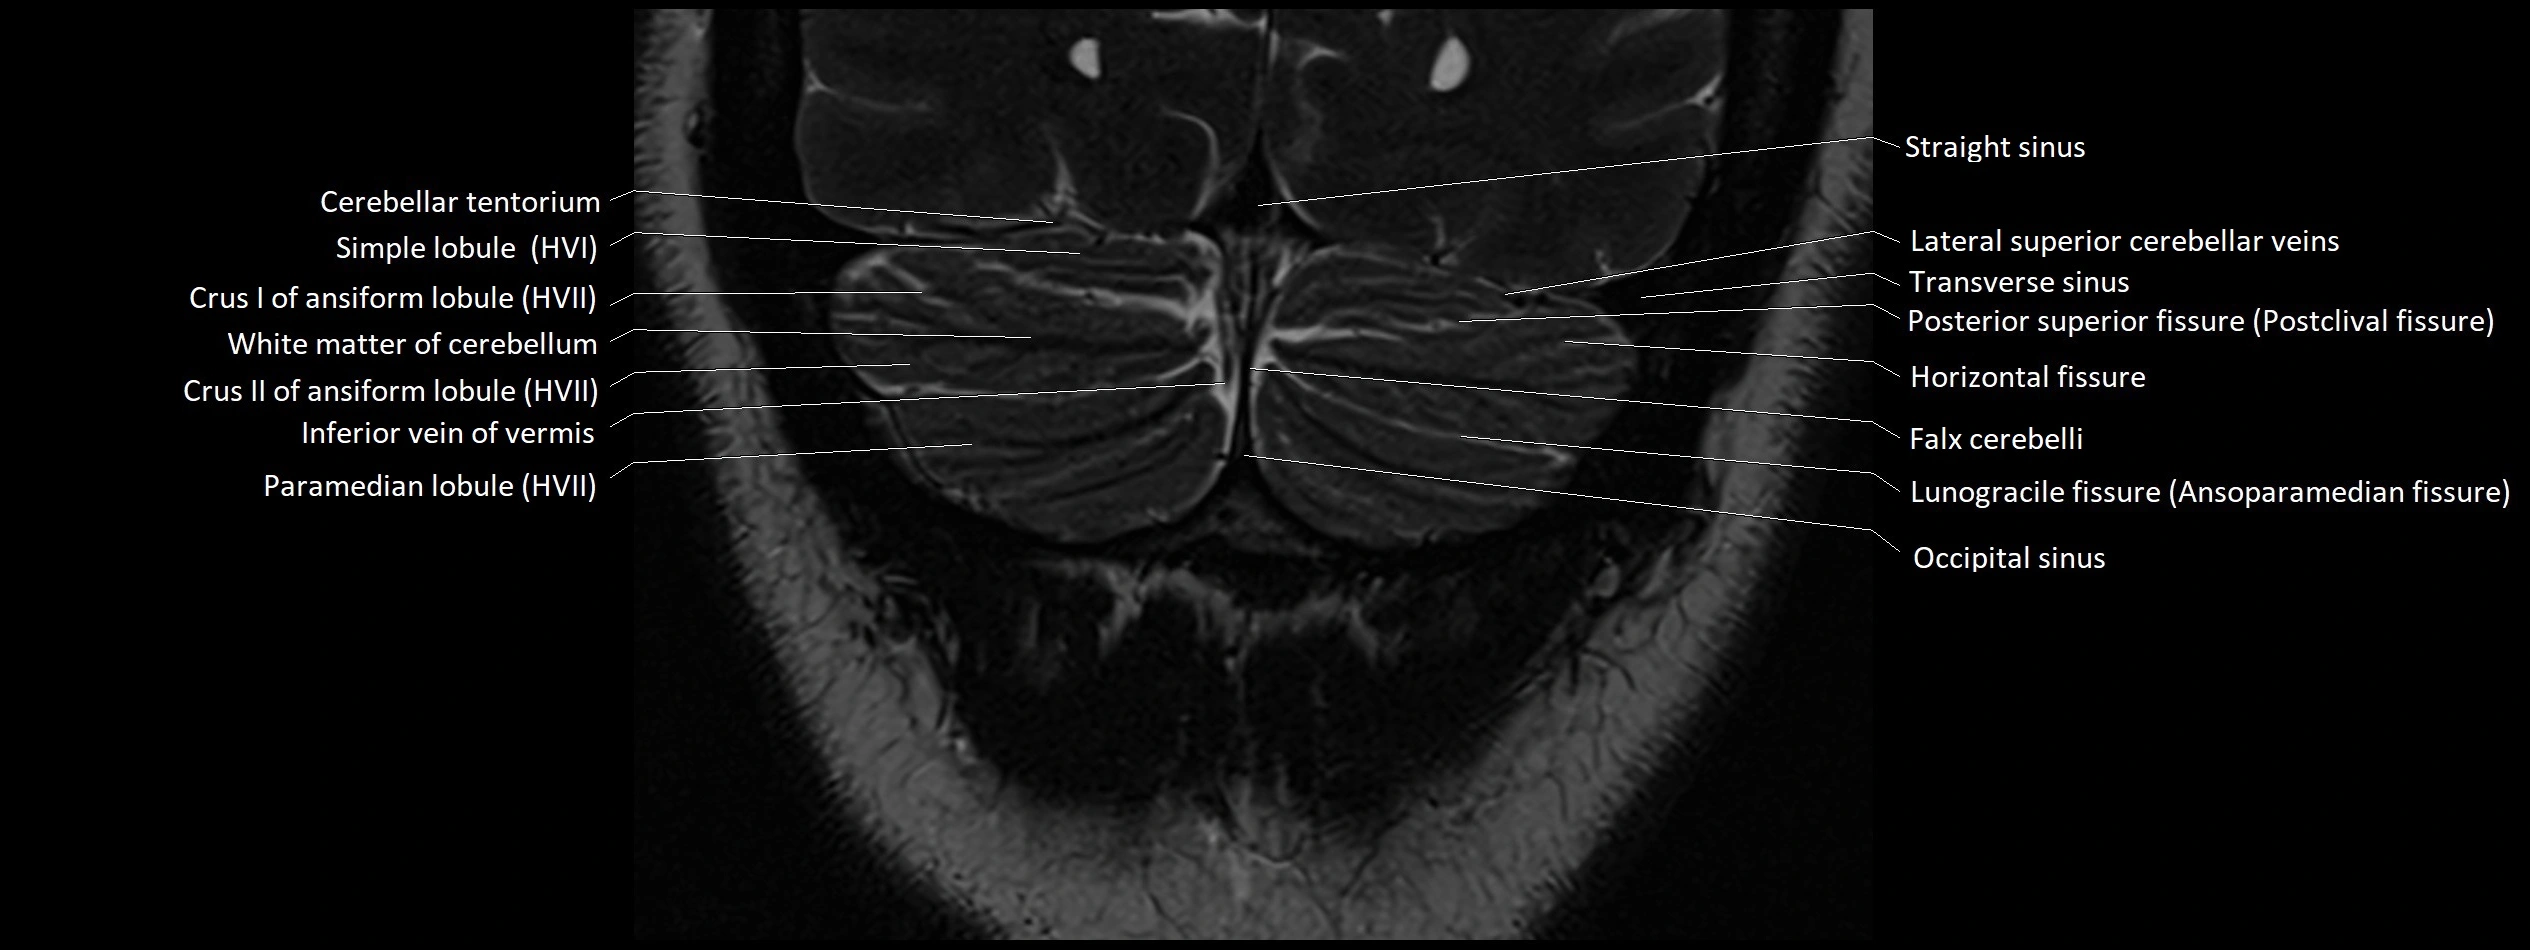

MRI images